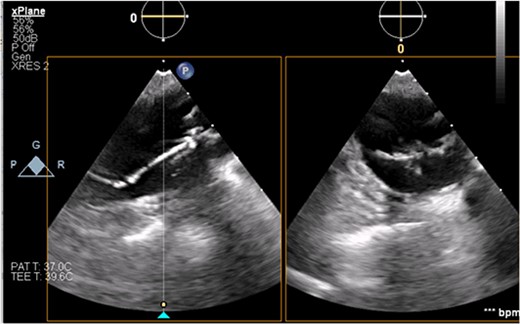

The patient’s milrinone dose was unable to be increased due to his risk for VT and his marginal blood pressures. A 50 cc 8 French left axillary IABP with proximal and distal markers was placed under fluoroscopy and transesophageal echo (TEE) guidance to prevent worsening of end-organ dysfunction and cardiogenic shock. About 3.5 weeks later, the patient received a heart transplant. His 20 gauge right radial arterial catheter was used for monitoring. There were no identifiable changes in the arterial line and the pressure waveforms. The patient was ambulatory in the intensive care unit (ICU) and showed no signs of decreased perfusion. After induction of general anesthesia, TEE showed the IABP in his aortic arch and ascending aorta with its tip placed proximally in the descending aorta (Figs 1 and 2).

TEE guidance and fluoroscopy were used during the insertion of this patient’s left axillary IABP. The TEE note post-IABP insertion states that ‘the balloon is seen from the distal end of the aortic arch extending into the descending aorta.’ A same-day post-insertion CXR in the ICU showed a shortened IABP at about 5.1 cm long, indicating that the balloon must have been folded over itself to allow both markers to be so close to each other (Fig. 4).